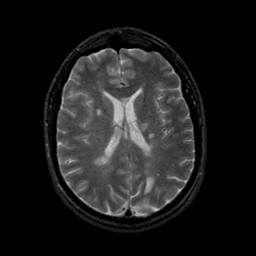

MR Study #9, April 14, 1991 -- Slice #30